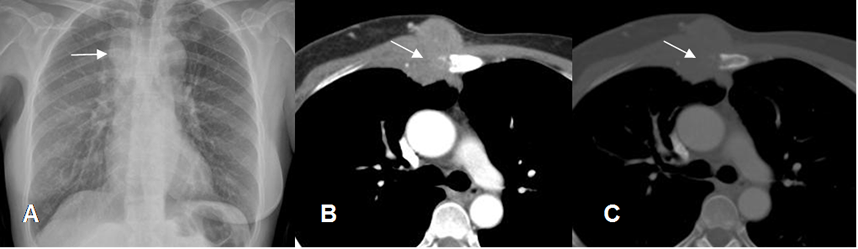

Fig 38. Lesiones extrapleurales.

A y B: Rx PA. Imágenes densas y de bordes bien definidos, que forman ángulos obtusos con la pared costal, indicando ubicación extrapleural.

Fig 39. Lesión extrapelural.

A: Rx PA y B: TAC axial. Imagen densa con ángulos obtusos, que ocasiona destrucción del arco costal, lo que confirman su localización extrapleural.